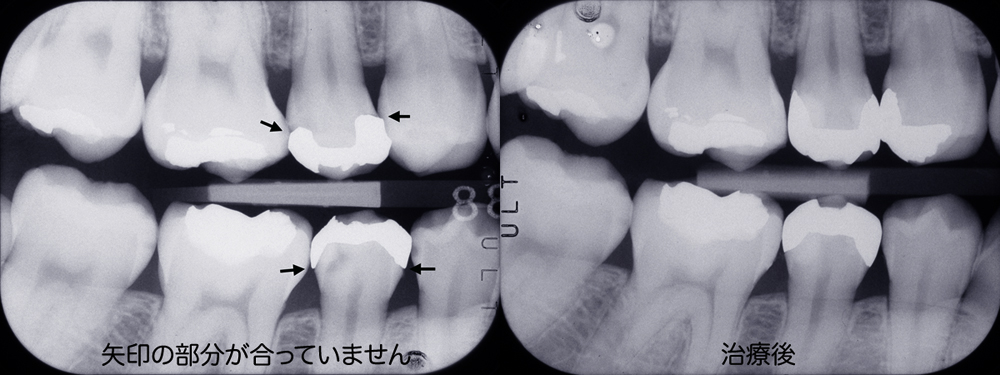

入れた歯の噛み合わせがおかしい、物がよくはさまる、糸楊枝が引っかかるなどの経験をしたことのある方も多いと思います。これは金属の被せ物や詰め物の精度の問題です。下の左右のレントゲン写真を比べてみましょう。レントゲンの中で白く抜けているのは金属の詰め物です。左側のレントゲンの詰め物は自分の歯と合っていないのがわかります。治療後の右側レントゲンの詰め物は歯とピッタリ合っているように見えます。糸楊枝を入れてもどこも引っかかりませんし違和感もありません。いつもこのように製作することが理想ですがそのためには衛生士が歯と歯肉をきれいにし、歯科医がきれいに歯を削り、歯形を取り、技工士が丁寧に補綴物を製作というすべてのステップをしっかり行うことが必要です。コストも労力もかかることですが須貝歯科医院ではすべてを院内で行うことで精度の高い物を作るように努力しています。残念なことですが現在の保険診療では完全な赤字部門で院内で賄うことで何とか頑張っています。保険で使用できる金属があまり良い物ではないこともあり、できるだけ保険外の適切な材料を使用して被せ物や詰め物を作っていただけるように患者さんにはお願いしています。

当医院で製作したブリッジですが糸楊枝を入れてもどこも引っかかりません。いつもこのように製作することが理想ですがそのためにはきれいに歯を削り、歯形を取り、丁寧に補綴物を製作というすべてのステップをしっかり行うことが必要です。 コストも労力もかかることですが須貝歯科医院では補綴物にこだわり精度の高い物を作るように努力しています。